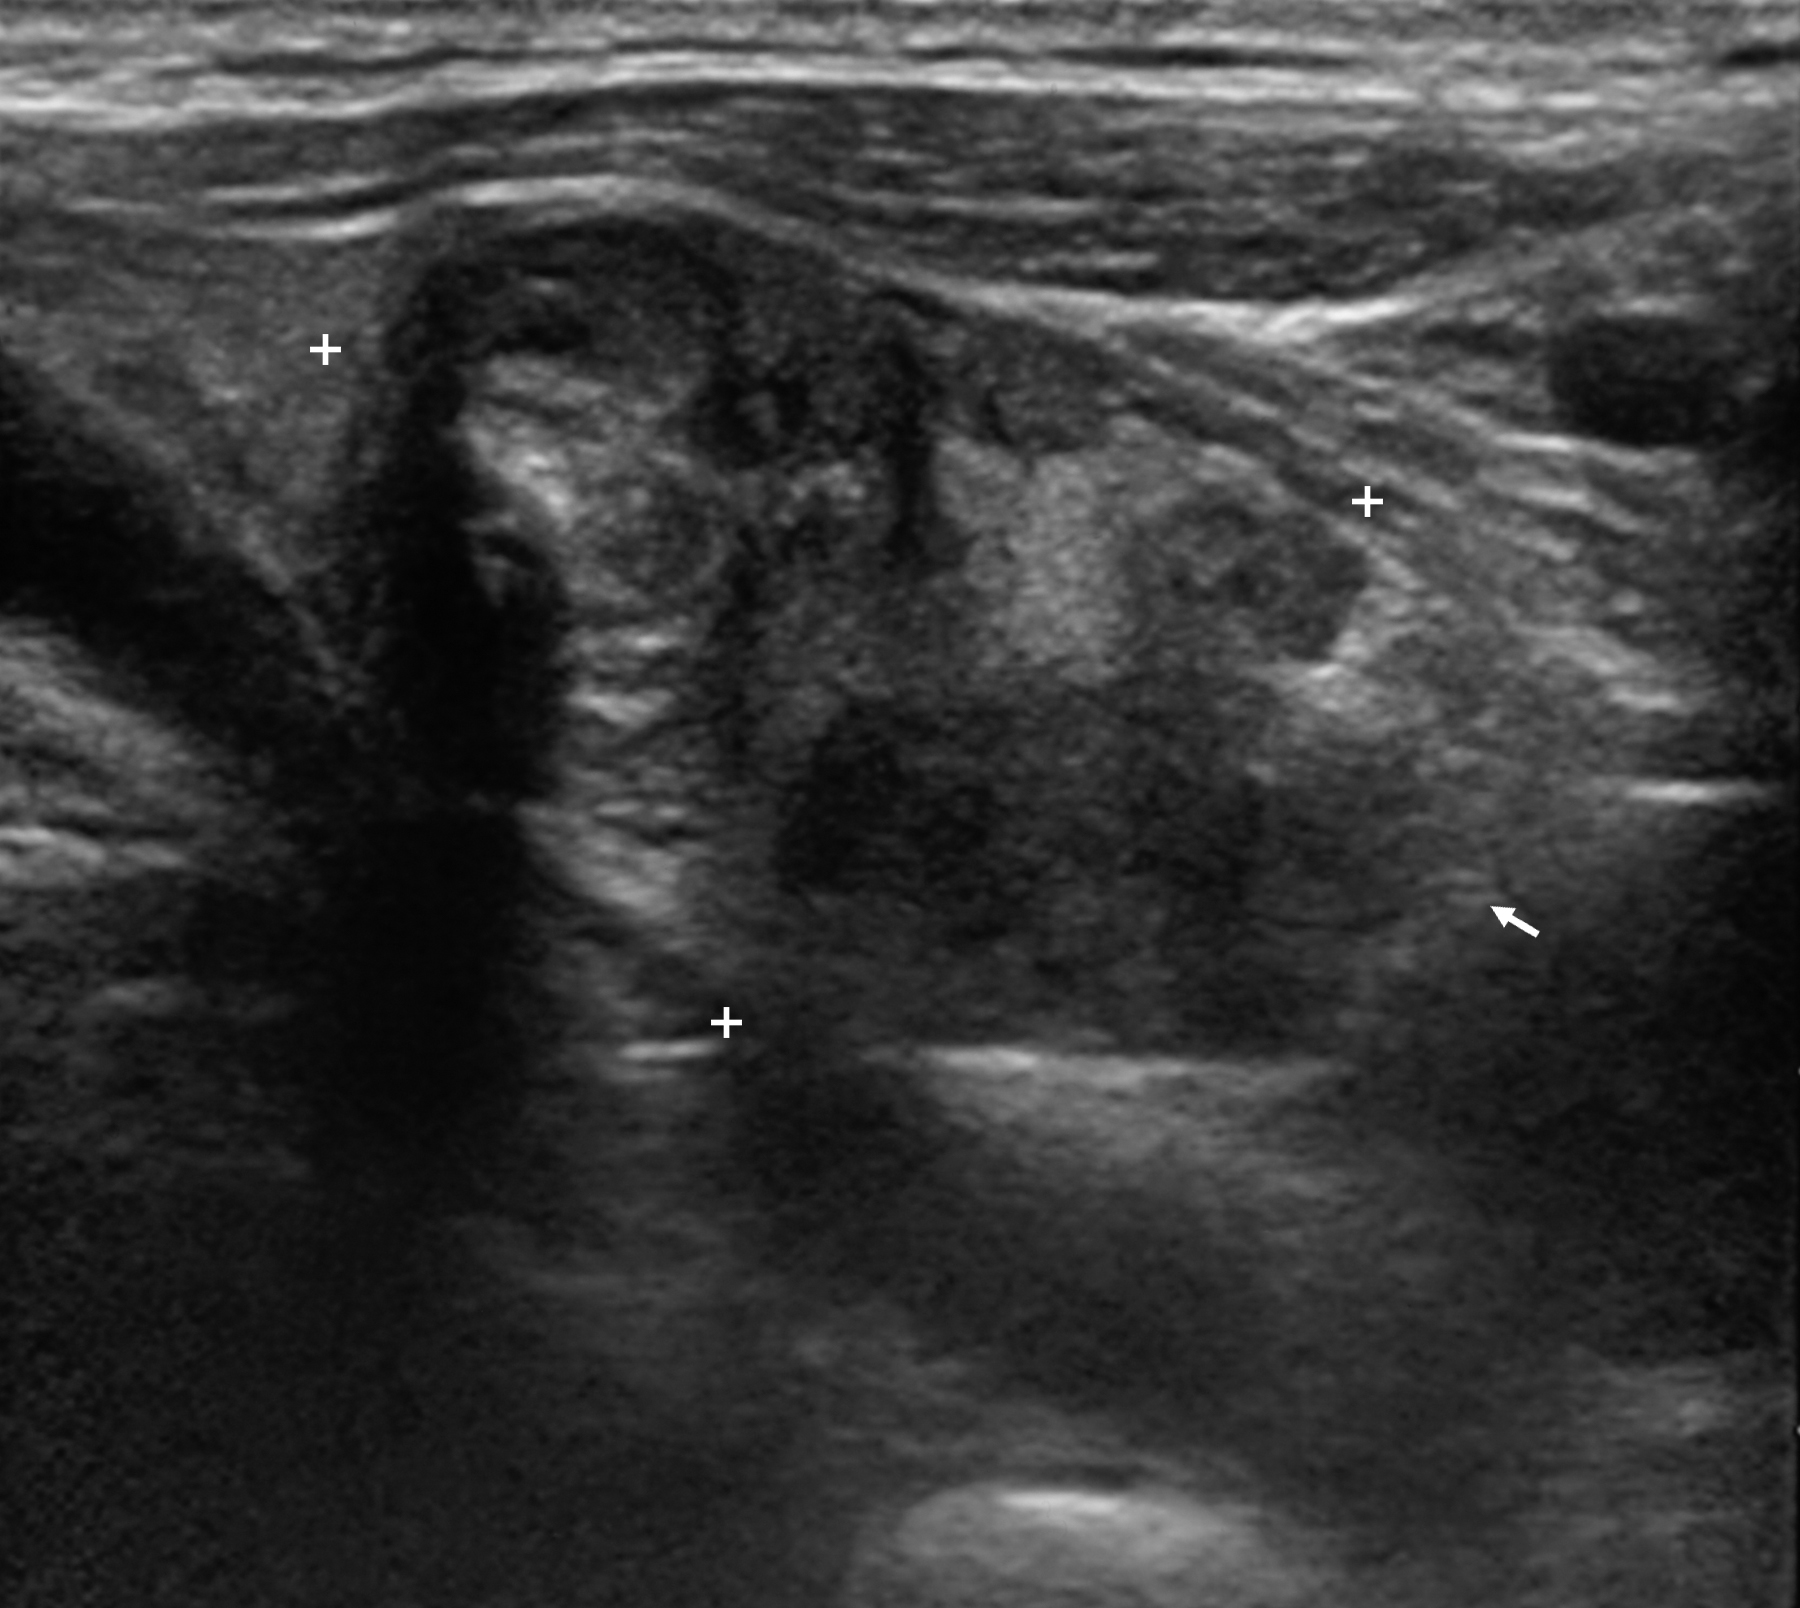

La aparición de metástasis a distancia en los cánceres diferenciados de tiroides es poco frecuente, y cuando se detectan en piel, suelen darse en el contexto de una enfermedad diseminada después de muchos años de evolución desde el diagnóstico. Se presenta el caso de una paciente de 77 años, sin enfermedad tiroidea conocida que debutó con una metástasis en región parietooccipital del cuero cabelludo en la que se identificó tejido tiroideo. En la ecografía tiroidea se identificó un nódulo informado como tumor folicular y el estudio de extensión precirugía fue negativo. Se le hizo tiroidectomía total más vaciamiento ganglionar del compartimento central y el estudio AP fue informado de carcinoma mixto folicular-papilar sin afectación ganglionar. En el RCT post-I131 (dosis de 104,7 mCi) se detectaron micrometástasis pulmonares, y a los 2 meses de una segunda dosis de I131 (125 mCi), la tiroglobulina fue indetectable.